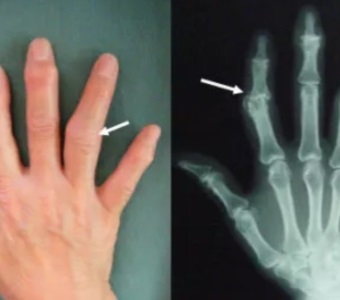

헤버든 결절, 부차드 결절

손가락의 첫번째 즉 제일 위 끝쪽 관절에 손가락마디통증 및 부종, 저림, 변형이 발생하는 질환을 말합니다. 그리고 두번째 마디에 생기면 부차드 결절이라고 합니다.

결절이라는 것은 뼈에 생긴 혹 같은 것으로 손가락마디 관절이 부어서 통증 느끼는 증상 뿐만 아니라 물집이 생기기도 합니다. 증상에 따라 개인차는 있지만 관절 연골 마모, 관절 사이가 좁이지면서 서서히 뼈의 변형이 나타나는 질환 입니다.

손가락마디통증 원인 중 이 헤버든 결절과 부차드 결절에 걸리면 손가락을 제대로 움직이지 못하게 되고 주먹을 쥐기도 힘들어지면서 일상생활에 곤란을 겪을 수 있게 됩니다. 자기면역질환 중 하나인 류마티스관절염과 비슷해서 구분하기 힘들 수 있습니다.